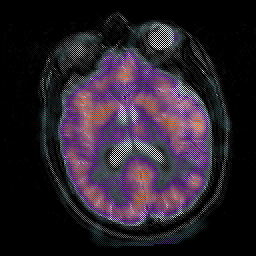

Subacute Stroke, overlay -- Slice #14

[Home][Help][Clinical] Slice 14